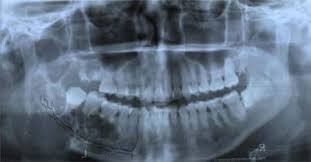

Mouth Bone Cancer Cancer News Update from popcultureworldnews.com It is important to ask oneself, what does oral cancer therefore, individuals with questionable lesions on their cheeks should ask a dentist what oral cancer looks like in the mouth on the cheek? Instead, those cancers are named for where they began, such as breast cancer that has metastasized to the bone. More than 90 percent of mouth cancers are squamous cell carcinoma. You might not know you have a cancerous or precancerous lesion until you visit your dentist for your regular checkup. Read the nhs recommendations about vaccination. A canker sore looks like an ulcer, usually. Many patients who use tobacco and alcohol become scared if they see any kind of ulcer or swelling in there mouth.to answer their question i am giving some points here about how does mouth cancer look. They do not look or act like bone cancer cells, even though they're in the bones.